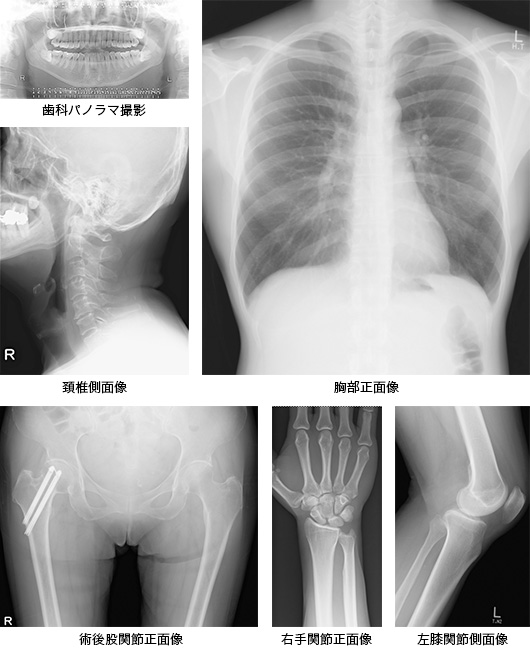

一般撮影部門

医療技術の進歩と共に画像診断機器の技術革新は目覚ましく、臨床において画像診断の果たす役割は著しく拡大しています。なかでもX線撮影は古くから医療に用いられており、様々な病気の初期診断において欠かすことのできない重要な検査の一つです。定期健康診断において行われる胸部X線撮影が最も代表的で、頭部、腹部,骨盤,四肢など全身のあらゆる骨や関節の様々なX線撮影を行っています。

「X線写真とは」

X線写真ができる過程を簡単に説明します。人体を構成する物質を大まかに分類すると骨・筋肉・脂肪・空気で構成されています。X線装置から照射されたX線が体内を透過する過程で骨・筋肉・脂肪など、様々な密度の異なる組織により減弱されるため、そのX線減弱の違いを白黒の濃淡で画像化したものを一般的にX線写真と言います。

画像参考例

「一般撮影機器の紹介」

放射線診断科(B1)の一般撮影機器は、2012年9月に全面的に更新されました。超高画質を実現するFPD(フラットパネルディテクタ)とオートポジショニング機能を搭載した最新鋭の一般撮影システムは、患者様に安心して受診していただけるような安全設計と低被ばく化、更には検査の高効率化と省力化に優れています。

「機器の主な特徴」

一般撮影室および乳房撮影室を含めた全撮影室が一新されました。一般撮影装置の特徴であるFPDでは、X線が直接電荷信号に変換されるため信号の劣化がなく、非常に高解像度で鮮明なフルデジタル画像が即時表示されます。また、このシステムはオートポジショニング機能が搭載されており、住友病院独自の撮影プログラムにセッティングされた一管球システムです。その他に、無用な被ばく線量を低減させる機構として、撮影部位に応じてコリメータのフィルターが連動して切り替わり最適な線量に自動設定されます。皮膚表面線量の算出可能な線量計(Exposure index機能)が搭載されているため、瞬時にX線撮影線量が表示され確認することができます。これらの機能は、検査時間の短縮と必要最低限のX線量で撮影することに繋がり、患者様と医療スタッフにとってなくてはならない機能です。良好な操作性および即時画像表示による信頼性、他のモダリティーや院内外を繋ぐネットワーク対応できる親和性の高い装置によって、一般撮影部門で発生する全ての画像は、高精細モニタで観察、検像作業を行ったうえで各診療部門へ画像提供を行っています。